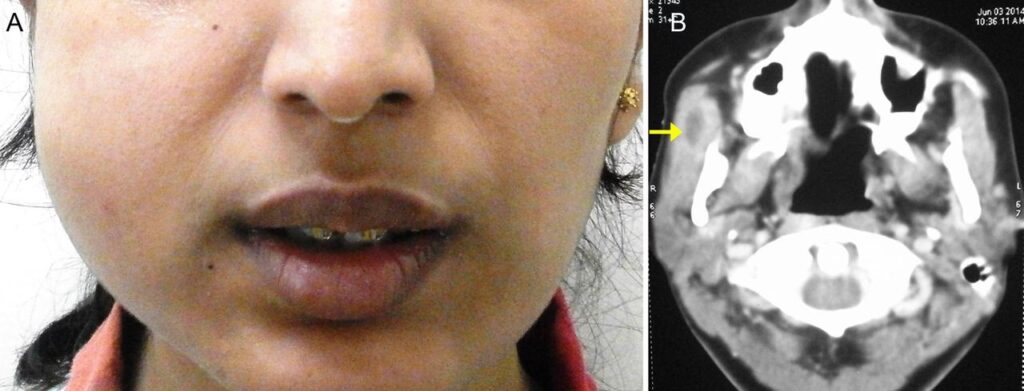

Tuberkuløs osteomyelitis er sjælden og udgør mindre end 2% af skelettuberkulose. Involvering af kæben er endnu sjældnere. Underkæben rammes hyppigere end overkæben, især i alveolær- og vinkelregionerne. Infektionen kan spredes direkte fra inficeret spyt, gennem en ekstraktionssokkel, en slimhindeåbning ved en frembrydende tand, ved regional udvidelse fra bløddelslæsioner eller hæmatogent. TB i kæben forårsager langsom nekrose af knoglen og dannelse af en subperiosteal absces, der viser sig som en smertefri, blød hævelse. Denne absces kan briste og danne enkelte eller multiple fistler intraoralt eller ekstraoralt. Diagnosen er en betydelig udfordring, da udstrygninger for syrefaste baciller ofte er negative. Røntgenbilleder kan vise et diffust radiolucent billede, erosion af kortikalpladen eller et "ormædt" udseende. Behandlingen består af antituberkuløs behandling og eventuelt kirurgisk debridering.

TB i kæbeleddet er ekstremt sjældent. Den kliniske præsentation er uspecifik og kan ligne osteomyelitis, arthritis eller kræft. Symptomerne udvikler sig snigende med smerte, stivhed i leddet og hævelse. Diagnosen stilles normalt ved hjælp af dyrkning, farvning og billeddannelse som MR-scanning, der kan påvise pus i leddet på et tidligt stadie. En biopsi er ofte nødvendig for at bekræfte diagnosen.